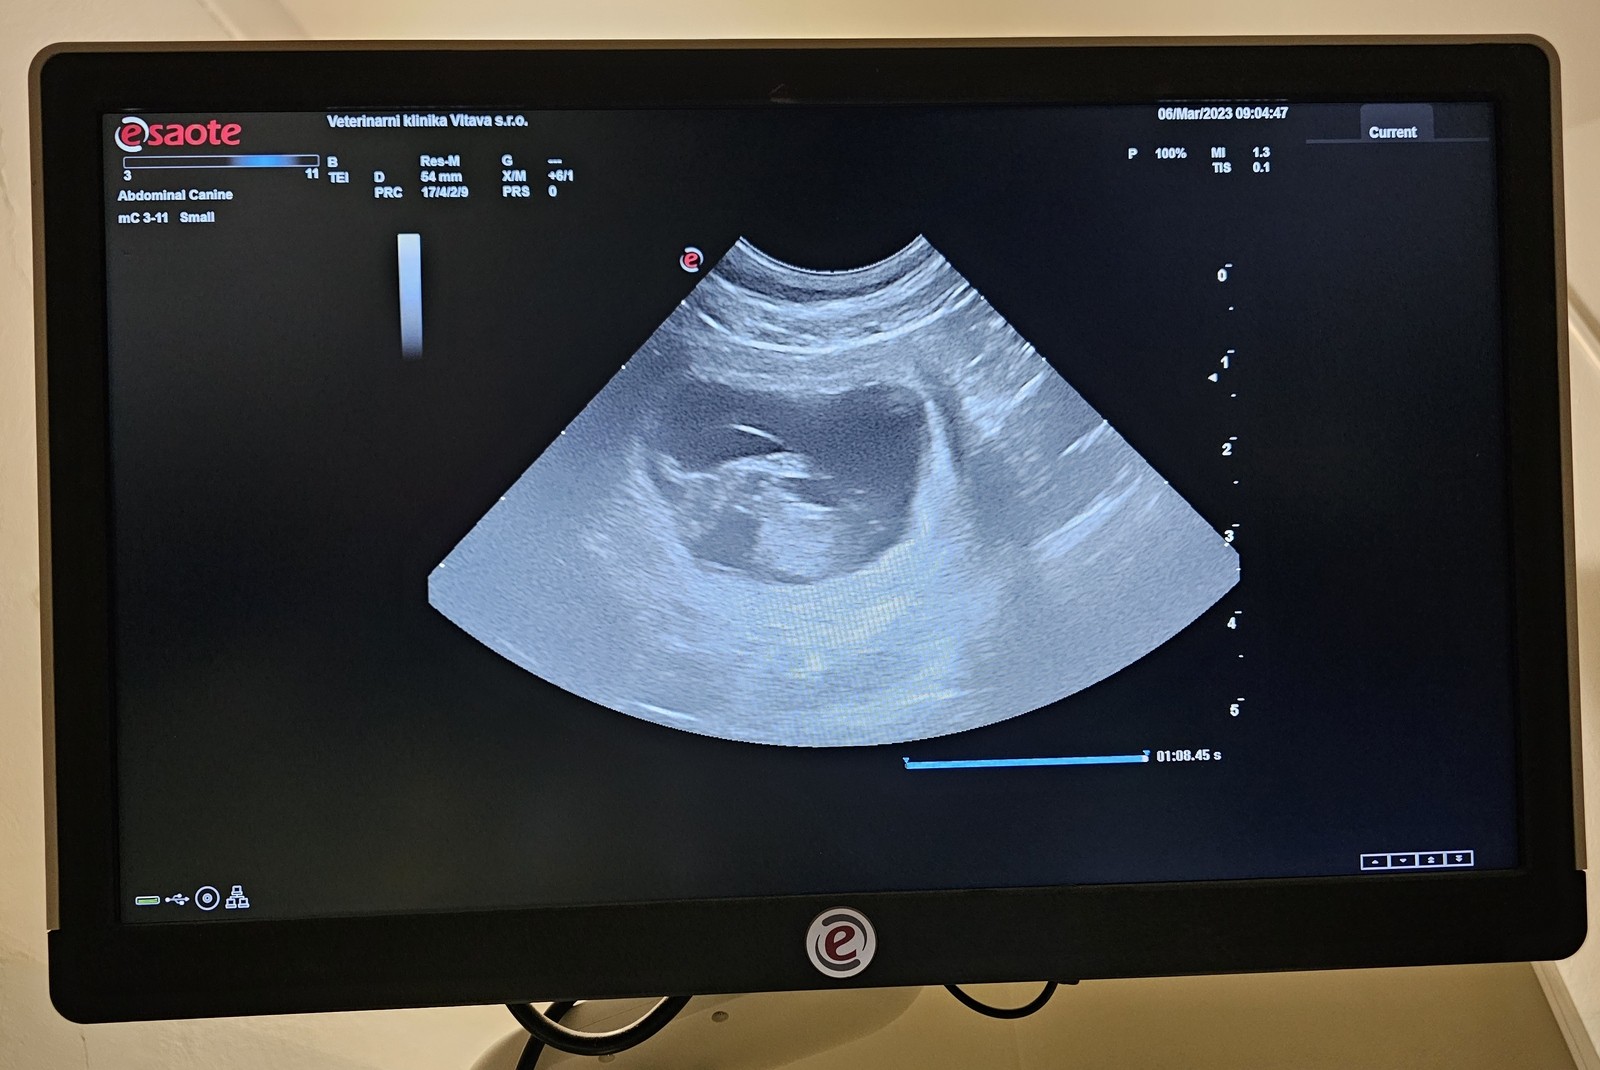

6. března 2023 - Ranní sonografie potvrdila březost u Abynky! Ukázala se nám minimálně 4 štěňátka, určitě jsou v bříšku pejskové i fenky.